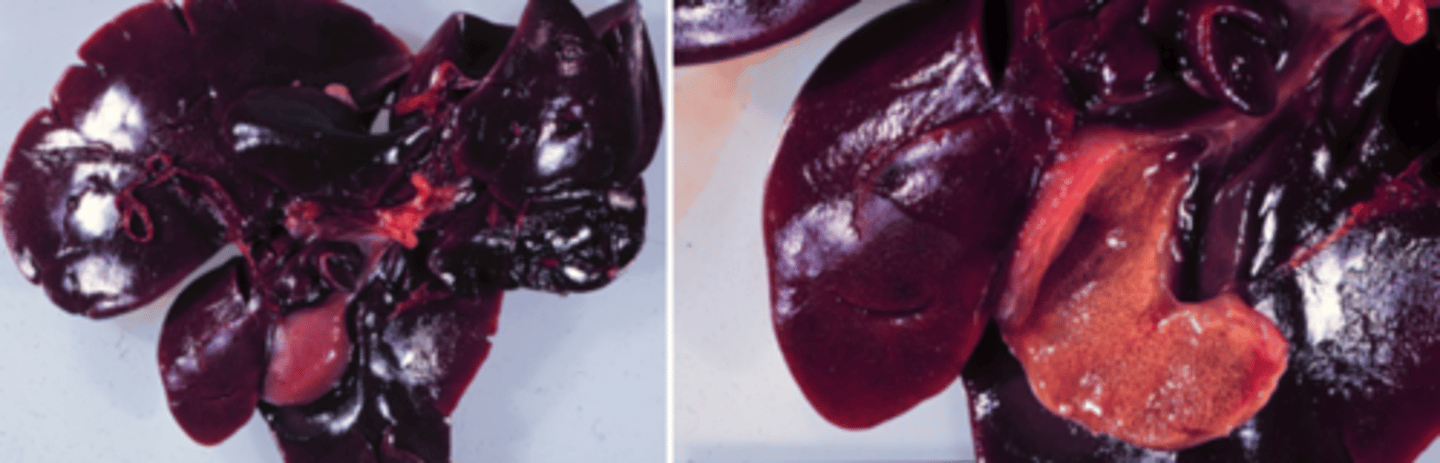

Akut dissemineret nekrose

vævet er tørt

Typisk hæmatogen spredning

Lever fra okse, hvad er den patoanatomiske diagnose?

Akut multifokal massiv lever nekrose

Lever fra okse, hvad er den patoanatomiske diagnose?